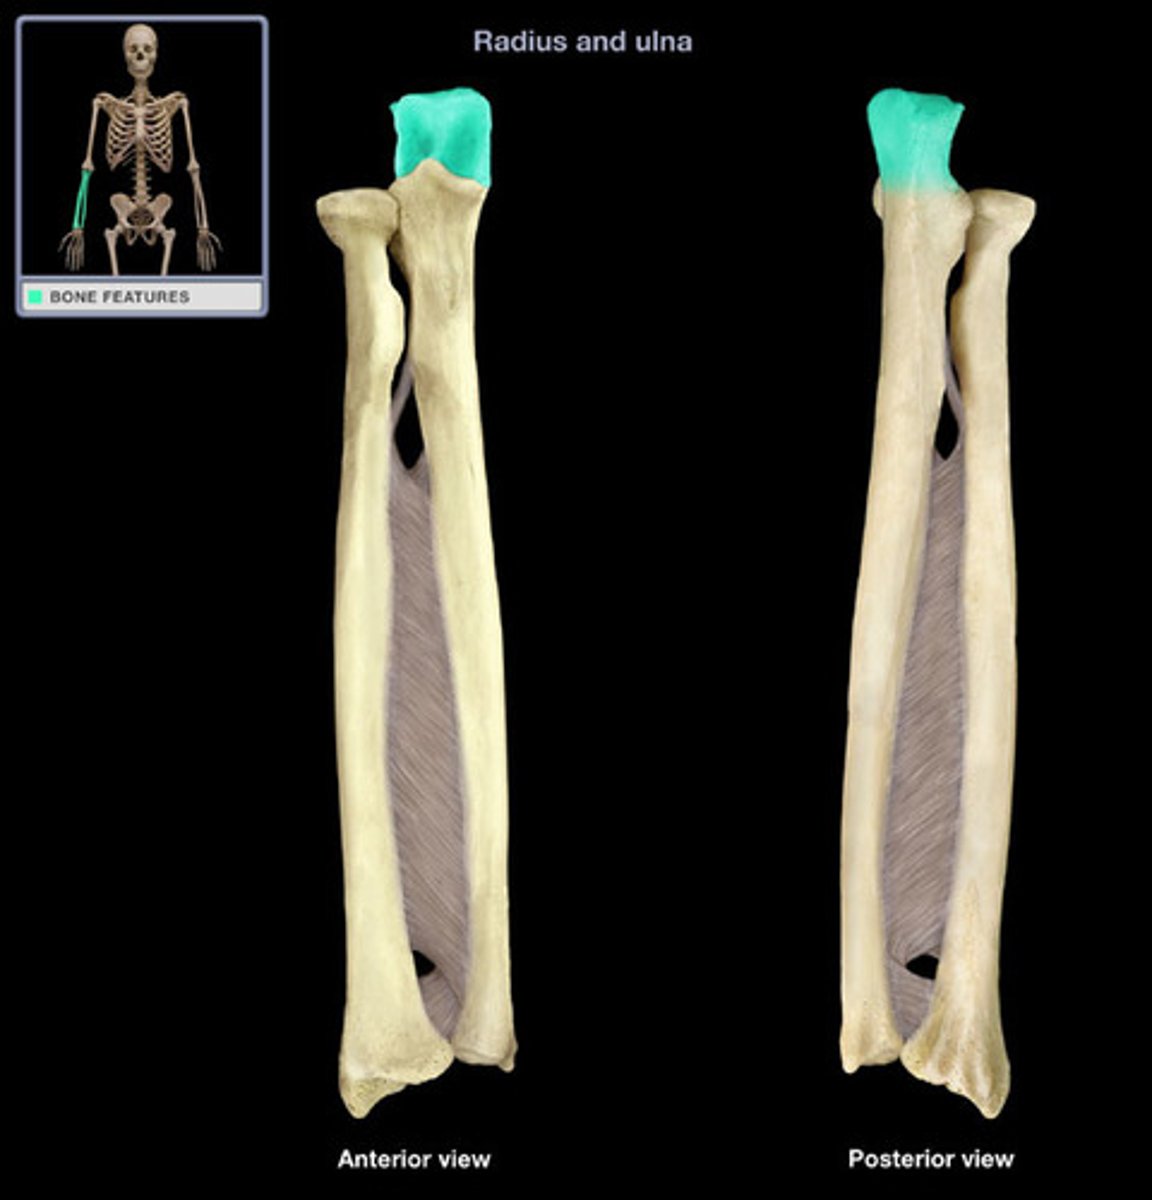

Bones of the forearm:

radius and ulna

Characteristics of the forearm:

- contains 2 bones

- radius can pivot on the ulna (supination and pronation) due to their parallel position

What is the radius capable of doing?

Can pivot on the ulna (supination and pronation) due to their parallel position

Location of the radius:

Lateral & shorter of the forearm

What does the radius articulate with?

- Articulate with the ulna (proximally and distally)

- articulate with carpal bones on the distal side of radius

What structure of the upper extremities does the radius form?

Forms the wrist joint

What does the radius control in the forearm?

Controls supination and pronation

Head of the radius:

Articulates with the capitulum of humerus and with the radial notch of the ulna

Neck of the radius:

Inferior to the head

Shaft of the radius:

Gets thicker distally opposite to the ulna

Ulnar notch of the radius:

Articulates with the head of the ulna

Radial styloid process of radius:

Distal ending on lateral side of the shaft of the radius